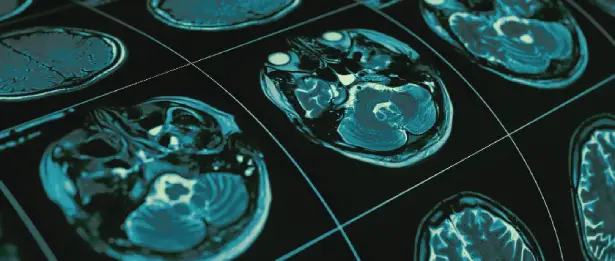

PET-CT; PET (Pozitron Emisyon Tomografisi ) ve CT'nin (Bilgisayarlı Tomografi) birleşiminden oluşan, fonksiyonel düzeydeki görüntüleri kesitsel anatomik bilgiler ile değerlendiren bir sistemdir. PET, hücrelerin fonksiyon ve metabolizması hakkında bilgi verirken; CT boyut, yerleşim ve yoğunluk gibi anatomik veriler sağlar.

Onkoloji hastalarında; iyi-kötü huylu kitlelerin ayrımını sağlamada, kanserin evrelendirilmesinde, tümörün habaset derecesinin organ içerisinde yaygınlığının, tüm vücut metastazlarının belirlenmesinde, nüksün saptanmasında, tedavi yönteminin seçilmesinde, tedavi cevabının değerlendirilmesinde, radyoterapi planlamasında gerçek tümör volümünün belirlenerek hedeflenmesi doğru yerin doğru dozda ışınlanmasını sağlamada kullanılır. Tüm değerlendirmeler, sayısal bilgi ile destekler. Onkolojik hasta grubunda PET-CT, tek seferde tüm vücudu görüntüleyerek diğer tüm görüntüleme yöntemlerinin toplamından daha fazla bilgi veren bir yöntemdir.

Liv Hospital'de PET-CT, pozitron emisyon tomografisi ve bilgisayarlı tomografi'nin birleşimi olan ileri düzey bir görüntüleme teknolojisidir. Bu teknoloji, vücut içindeki hücresel aktiviteleri ve anatomik yapılardaki değişiklikleri detaylı bir şekilde gözlemleyerek teşhis ve tedavi planlamasına katkı sağlar. PET-CT, onkoloji, kardiyoloji ve nöroloji gibi birçok tıbbi alanın yanı sıra kanser taraması ve tedavi yanıtının değerlendirilmesinde kullanılır. Liv Hospital'de uzman sağlık ekibi tarafından yönetilen PET-CT taramaları, hastalara daha kesin ve kişiselleştirilmiş bir tedavi yaklaşımı sunma amacıyla kullanılır.